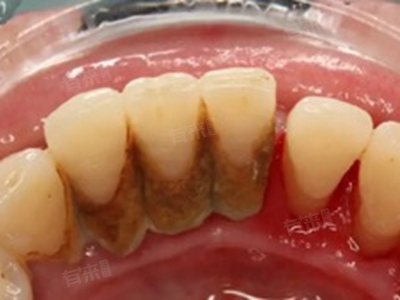

牙结石被自己抠下来后下牙出现小洞,可能是由于牙结石过多、牙齿缝隙、牙龈萎缩或牙齿龋坏等多种原因导致的。如果发现牙齿上有牙结石或出现小洞等异常情况,应及时前往口腔医院就诊,在医生的指导下进行治疗,比如超声波洗牙等,避免自行处理导致病情恶化。

1、牙结石过多:牙结石是附着在牙齿和牙龈边缘的矿物质沉积物,如果牙结石过多,可能会堵塞牙齿之间的缝隙,使相邻牙齿之间的间隙看起来不明显。当牙结石被抠掉后,原本被遮挡的缝隙就会显露出来,形成一个小洞。建议前往口腔医院进行超声波洗牙,彻底清除牙齿上的牙结石。洗牙后,缝隙可能会暂时变大,但随着时间的推移和牙龈的恢复,缝隙会逐渐变得不明显。

3、牙龈萎缩:牙结石的长期存在会刺激牙龈,导致牙龈萎缩。当牙结石被抠掉后,萎缩的牙龈无法立即恢复,会显得牙齿之间有一个洞。牙龈萎缩的治疗相对复杂,需要根据具体情况进行。轻度的牙龈萎缩可以遵医嘱通过洗牙、药物漱口等方法来缓解。如果牙龈萎缩严重,影响到牙齿的稳固性,可能需要进行手术治疗,如膜龈修复手术等。